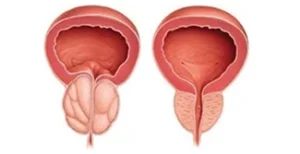

dos homens acima de 50 anos apresentam algum grau de Hiperplasia Prostática Benigna (HPB) — mesmo sem sintomas no início.

dos homens acima de 50 anos apresentam algum grau de Hiperplasia Prostática Benigna (HPB) — mesmo sem sintomas no início.

dos pacientes submetidos à prostatectomia robótica apresentam continência urinária preservada ou recuperada nos primeiros meses.

Técnica endoscópica avançada que remove o tecido prostático obstrutivo com mínimo sangramento, ideal para próstatas volumosas, substituindo cirurgias abertas convencionais.

Cirurgia robô-assistida para remoção completa da próstata e vesículas seminais, garantindo alta precisão, menor sangramento e melhor preservação da continência urinária e função sexual.

Indicação para próstatas extremamente aumentadas, permitindo excelente visualização cirúrgica, menor trauma tecidual e recuperação mais rápida.

Descubra métodos eficazes de tratamento de neoplasia de próstata conduzidos por Dr. Rodolfo G. Borges em Cuiabá-MT. Cuidado especializado aqui.

levar mais informação, clareza e tranquilidade aos meus pacientes, preparei este material explicativo sobre o Câncer de Próstata e as principais opções de tratamento cirúrgico, incluindo a CIRURGIA ROBÓTICA.